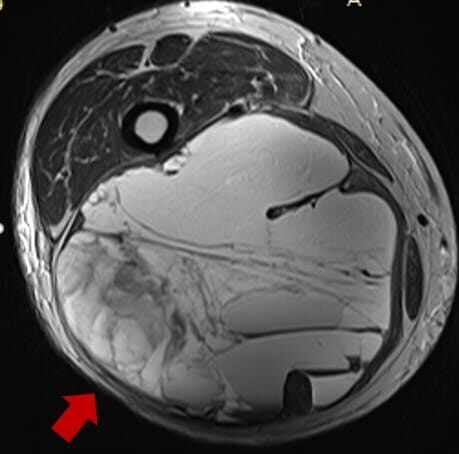

Soft tissue sarcoma is a rare type of cancer that develops in the connective tissues that support, surround, and protect the body's organs. These tissues include muscles, fat, nerves, tendons, blood vessels, and the lining of joints. Because soft tissue sarcomas can arise almost anywhere in the body, they often grow silently in the early stages, making early detection challenging.

This cancer typically appears as a painless lump, but as it grows, it may press on nearby nerves, organs, or muscles, causing discomfort or functional limitations. Soft tissue sarcomas include various subtypes such as liposarcoma, leiomyosarcoma, synovial sarcoma, and angiosarcoma—each with its own behavior, growth pattern, and treatment approach.

Diagnosis usually involves imaging tests like MRI or CT scans, followed by a biopsy to confirm the type of sarcoma. Treatment may include surgery, radiation therapy, chemotherapy, or advanced targeted therapies, depending on the tumor's size, location, and stage. With timely medical care from a multidisciplinary team, many patients achieve positive outcomes and improved quality of life.